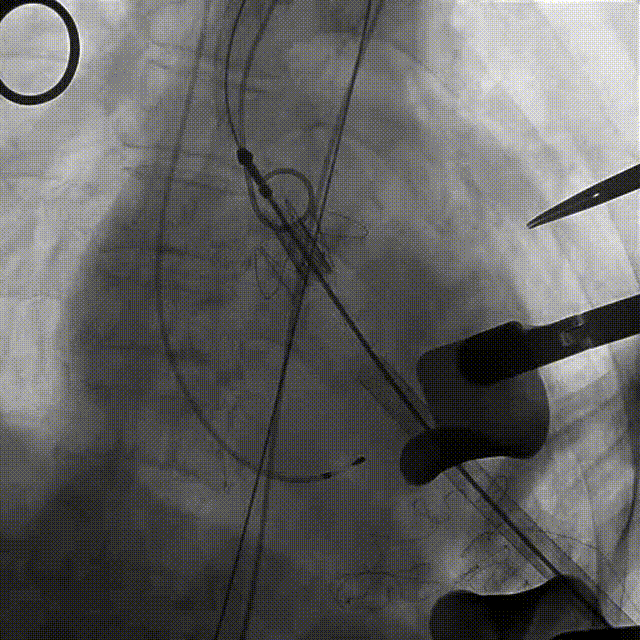

近日,中国人民解放军南部战区总医院王显悦教授、张本教授团队应用J-VALVE瓣膜完成一例高难度经心尖TAVI。患者为72岁男性,心脏超声示主动脉瓣重度狭窄伴轻度关闭不全,且二尖瓣中度狭窄。由于具有急性心力衰竭、高血压3级、肺气肿等其他疾病,且体重仅35公斤,对外科开胸手术耐受较差,风险极大,经过团队综合评估,决定行经心尖TAVI手术,拟植入25mm J-VALVE瓣膜。该患者存在升主动脉瓷化和左室流出道重度钙化,为手术增加了额外难度,术者团队凭借过硬的专业技能和细节处理能力,有效避免了术中可能存在的风险,并成功植入瓣膜。术后食道超声示无瓣周漏、无冠脉堵塞等并发症,患者症状明显缓解,手术顺利完成。

该患者升主动脉瓷化,左室流出道重度钙化。在TAVI手术过程中,导管和瓣膜的通过可能会对瓷化主动脉造成损伤,增加主动脉夹层、血管破裂等严重并发症风险;左室流出道的重度钙化会影响人工瓣膜与周围组织的贴合,使得瓣膜无法完全密封,从而增加瓣周漏的发生概率。

手术过程